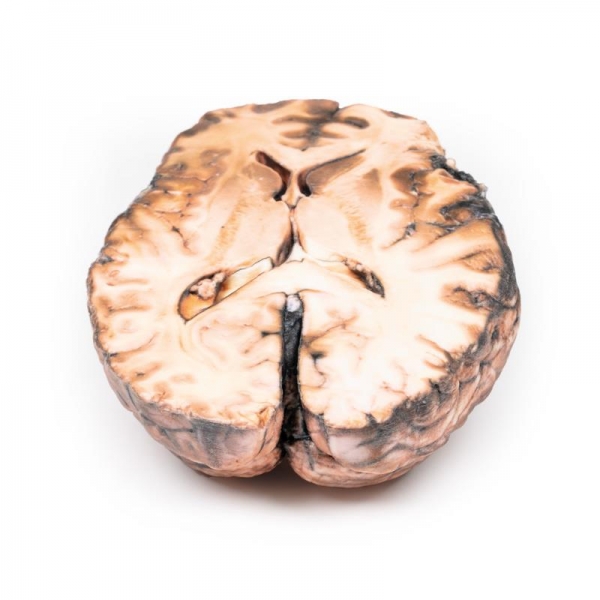

Pathologie

Das Präparat zeigt die Basalfläche des Gehirns. An der Einmündung der rechten inneren Karotis in die hintere Kommunikationsarterie befindet sich ein sackförmiges Aneurysma mit einem Durchmesser von 5 mm, das gerissen ist. In der unmittelbaren Umgebung der Cisterna magna und an der Unterseite des rechten Frontallappens befindet sich subarachnoidales Blut. Auf der linken Seite befindet sich ein ähnliches, nicht gerissenes Aneurysma. Der rechte Frontallappen scheint weicher und anterior brüchiger zu sein.

Aneurysmen der hinteren Kommunikationsarterie sind die dritthäufigsten Aneurysmen des Circulus Willis und können zur Kompression und Lähmung nahe gelegener Hirnnerven führen, wie in diesem Fall des VI. Die Nähe des ophthalmischen Abschnitts des Nervus trigeminus zum rupturierten Aneurysma kann bei diesem Patienten auch das plötzliche Auftreten von Schmerzen "hinter dem Auge" erklären. Der Gesichtsfelddefekt ist höchstwahrscheinlich auf eine Kompression des rechten Sehnerven zurückzuführen. Die klinischen Manifestationen des Schlaganfalls sind eine Folge des Gebiets der Großhirnrinde, deren Gefäßversorgung aufgrund des rupturierten Aneurysmas beeinträchtigt ist